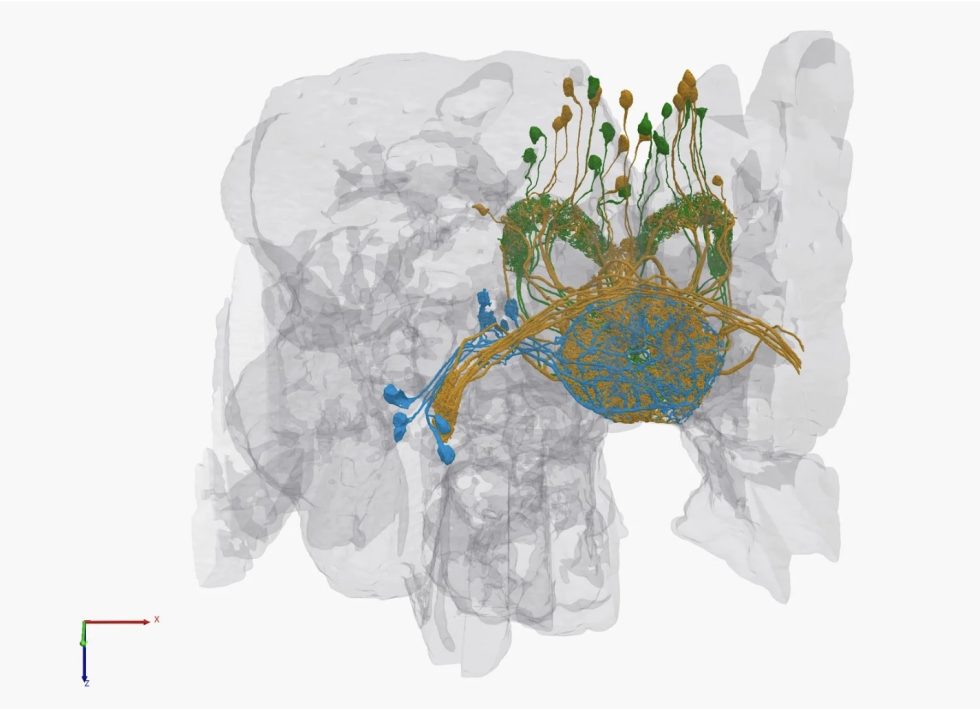

Коннектом мозга: визуализация связей и нейронных путей